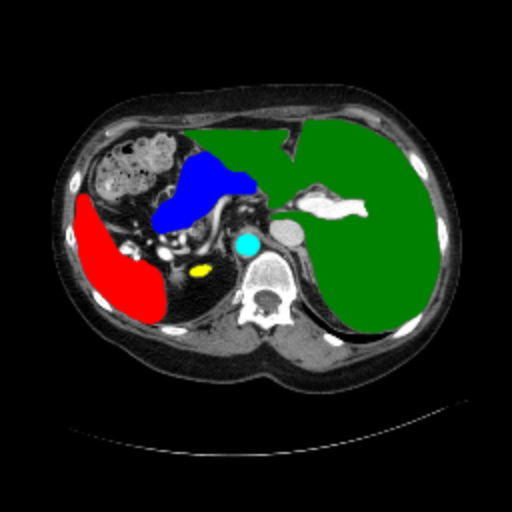

Figure 3 presents a qualitative comparison of segmentation performance on examples from the Synapse, BTCV, ACDC, and ISIC17 datasets. The first two examples (from Synapse) highlight variations in segmentation performance among U-Net, TransUnet, Mamba-Unet, and Swin-Unet. While Swin-Unet performs well in the first example, its performance decreases in the second example, particularly in segmenting the organ highlighted in blue. Additionally, it misclassifies background regions as the class highlighted in orange. In contrast, our approach demonstrates high robustness in segmenting all classes accurately and aligning well with the ground truth masks.

Across BTCV, ACDC, and ISIC17, the comparison methods exhibit varying performance depending on the task and class. For instance, Mamba-Unet struggles to segment multiple organs in BTCV, even misclassifying certain classes as others. In the ACDC dataset, both TransUnet and Mamba-Unet perform poorly in segmenting the three classes. In the last column (ISIC17), Swin-Unet oversegments the skin lesion compared to the ground truth. Unlike the comparison models, our approach consistently delivers effective segmentation across different tasks and datasets.

These qualitative findings further reinforce the quantitative results presented in the experimental section, demonstrating the effectiveness of our MambaCAFU model in handling binary and multi-class segmentation across diverse medical imaging modalities and tasks.

Slice GT Unet TransUnet Mamba-Unet Swin-UMamba MambaCAFU-V1

Figure 3: Visual comparison of segmentation examples from Synapse (first two examples), BTCV (3-4 examples), ACDC (5th example) and ISIC17 (last example). Columns: input slice, ground truth, Unet, TransUnet, Mamba-Unet, Swin-UMamba, and MambaCAFU-V1.